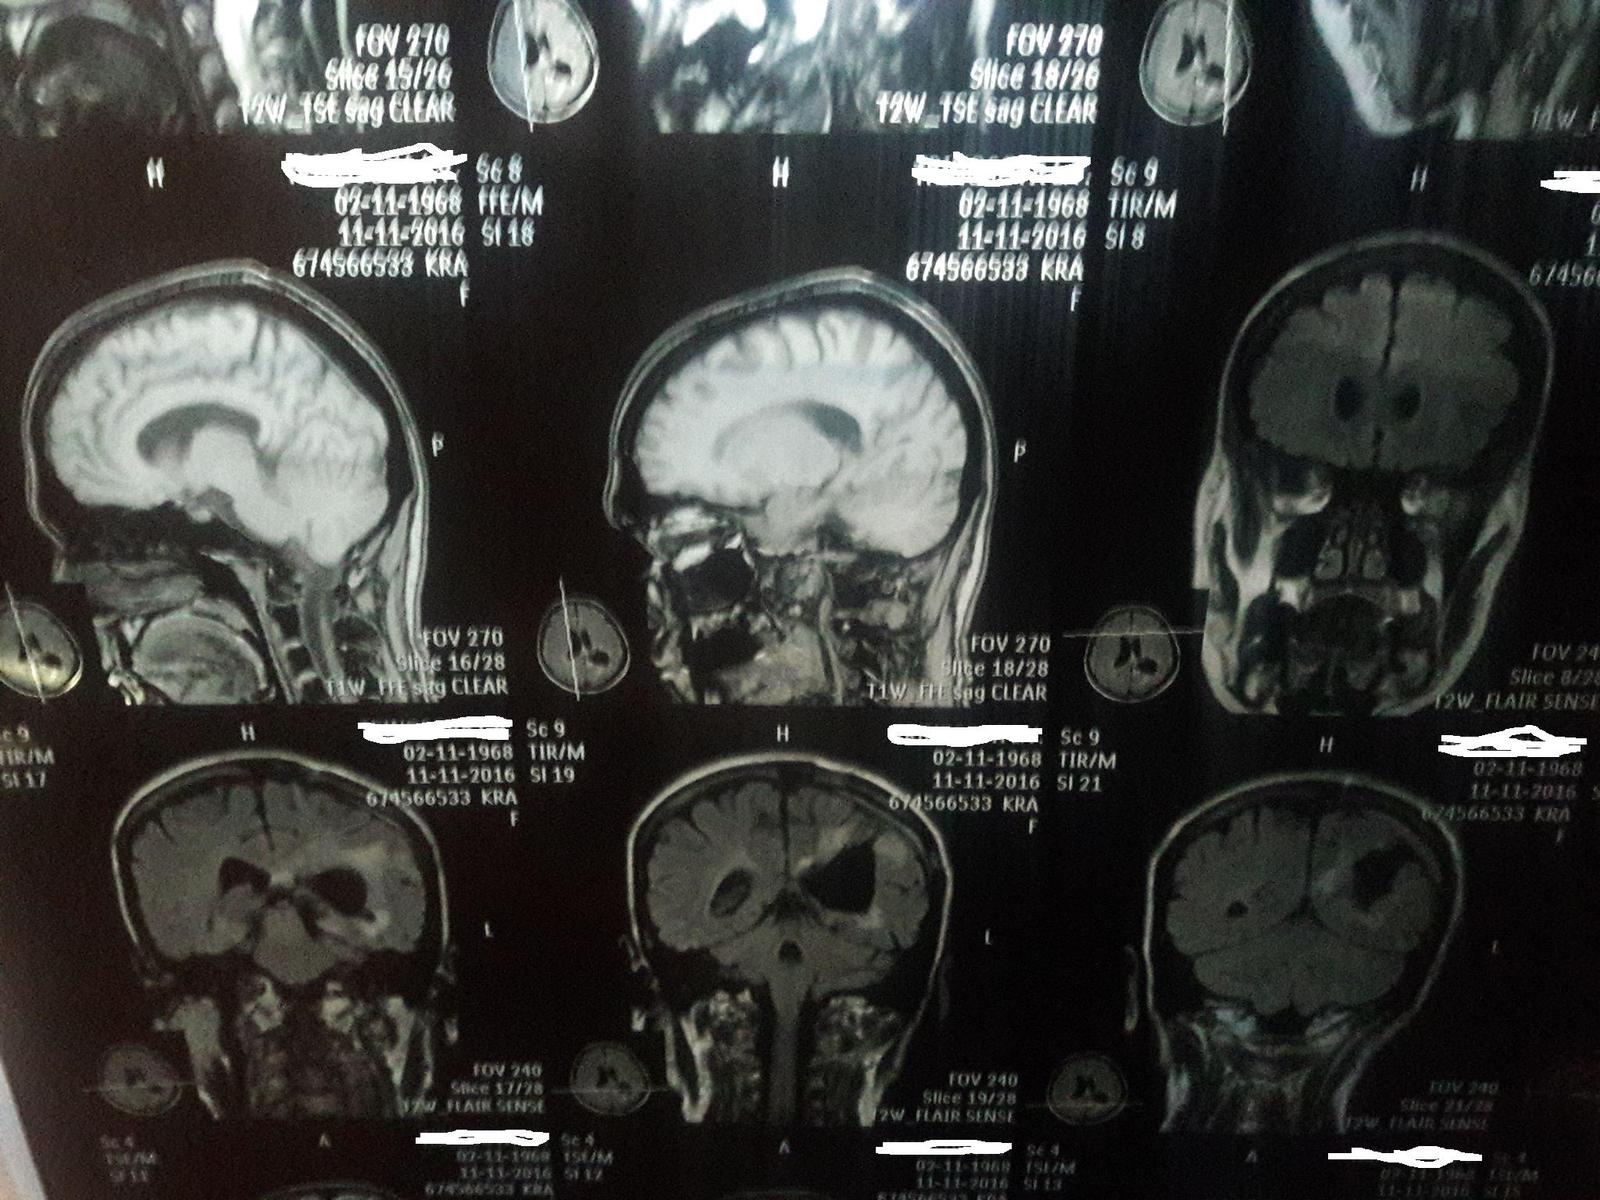

МРТ мозга...

а вот вам МРТ реального человека

P.S.(найди опухоль:D)

P.S.S. на втором снимке гематома после неё))

P.S.S.S фамилию замазал, т.к. МРТ матери